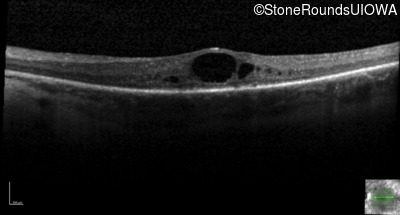

Optical Coherence Tomography - Left - 20/70 +1

Exemplar / OCT Stack